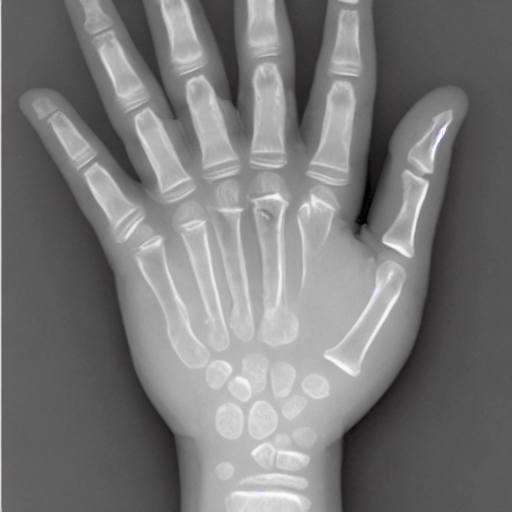

1. The patient had residual paralysis of the hand after poliomyelitis. It was necessary to stabilize the thumb with reference to the index finger. This was accomplished by placing a graft from the bone bank between the first and second metacarpals. The roentgenogram shows the complete healing of the graft one year later.

hand